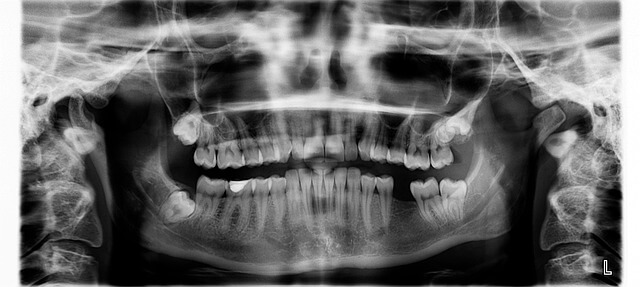

2. 잇몸치료 방법: 전문가가 권하는 단계별 접근

* 흔히 잇몸치료라고 하면 한 번의 진료로 끝날 거라 생각하지만 실제로는 단계별로 나누어 접근하는 경우가 많습니다. * 처음에는 간단한 세정으로 시작하고, 상태가 심하면 잇몸 깊은 곳까지 관리하는 정밀 치료가 필요하죠. * 제가 상담해봤을 때도 잇몸치료는 개인 상태에 따라 달라져서 획일적인 방식은 거의 없었습니다. * 결국 맞춤형으로 접근했을 때 결과가 훨씬 안정적이었습니다. * 이런 고민 하셨다면, 전문가의 조언을 듣고 내 상황에 맞는 단계별 방법을 선택하는 게 가장 현명한 길입니다.

- 기본 관리 단계

- 잇몸 깊숙한 치료 단계

- 정기 검사와 관리 단계